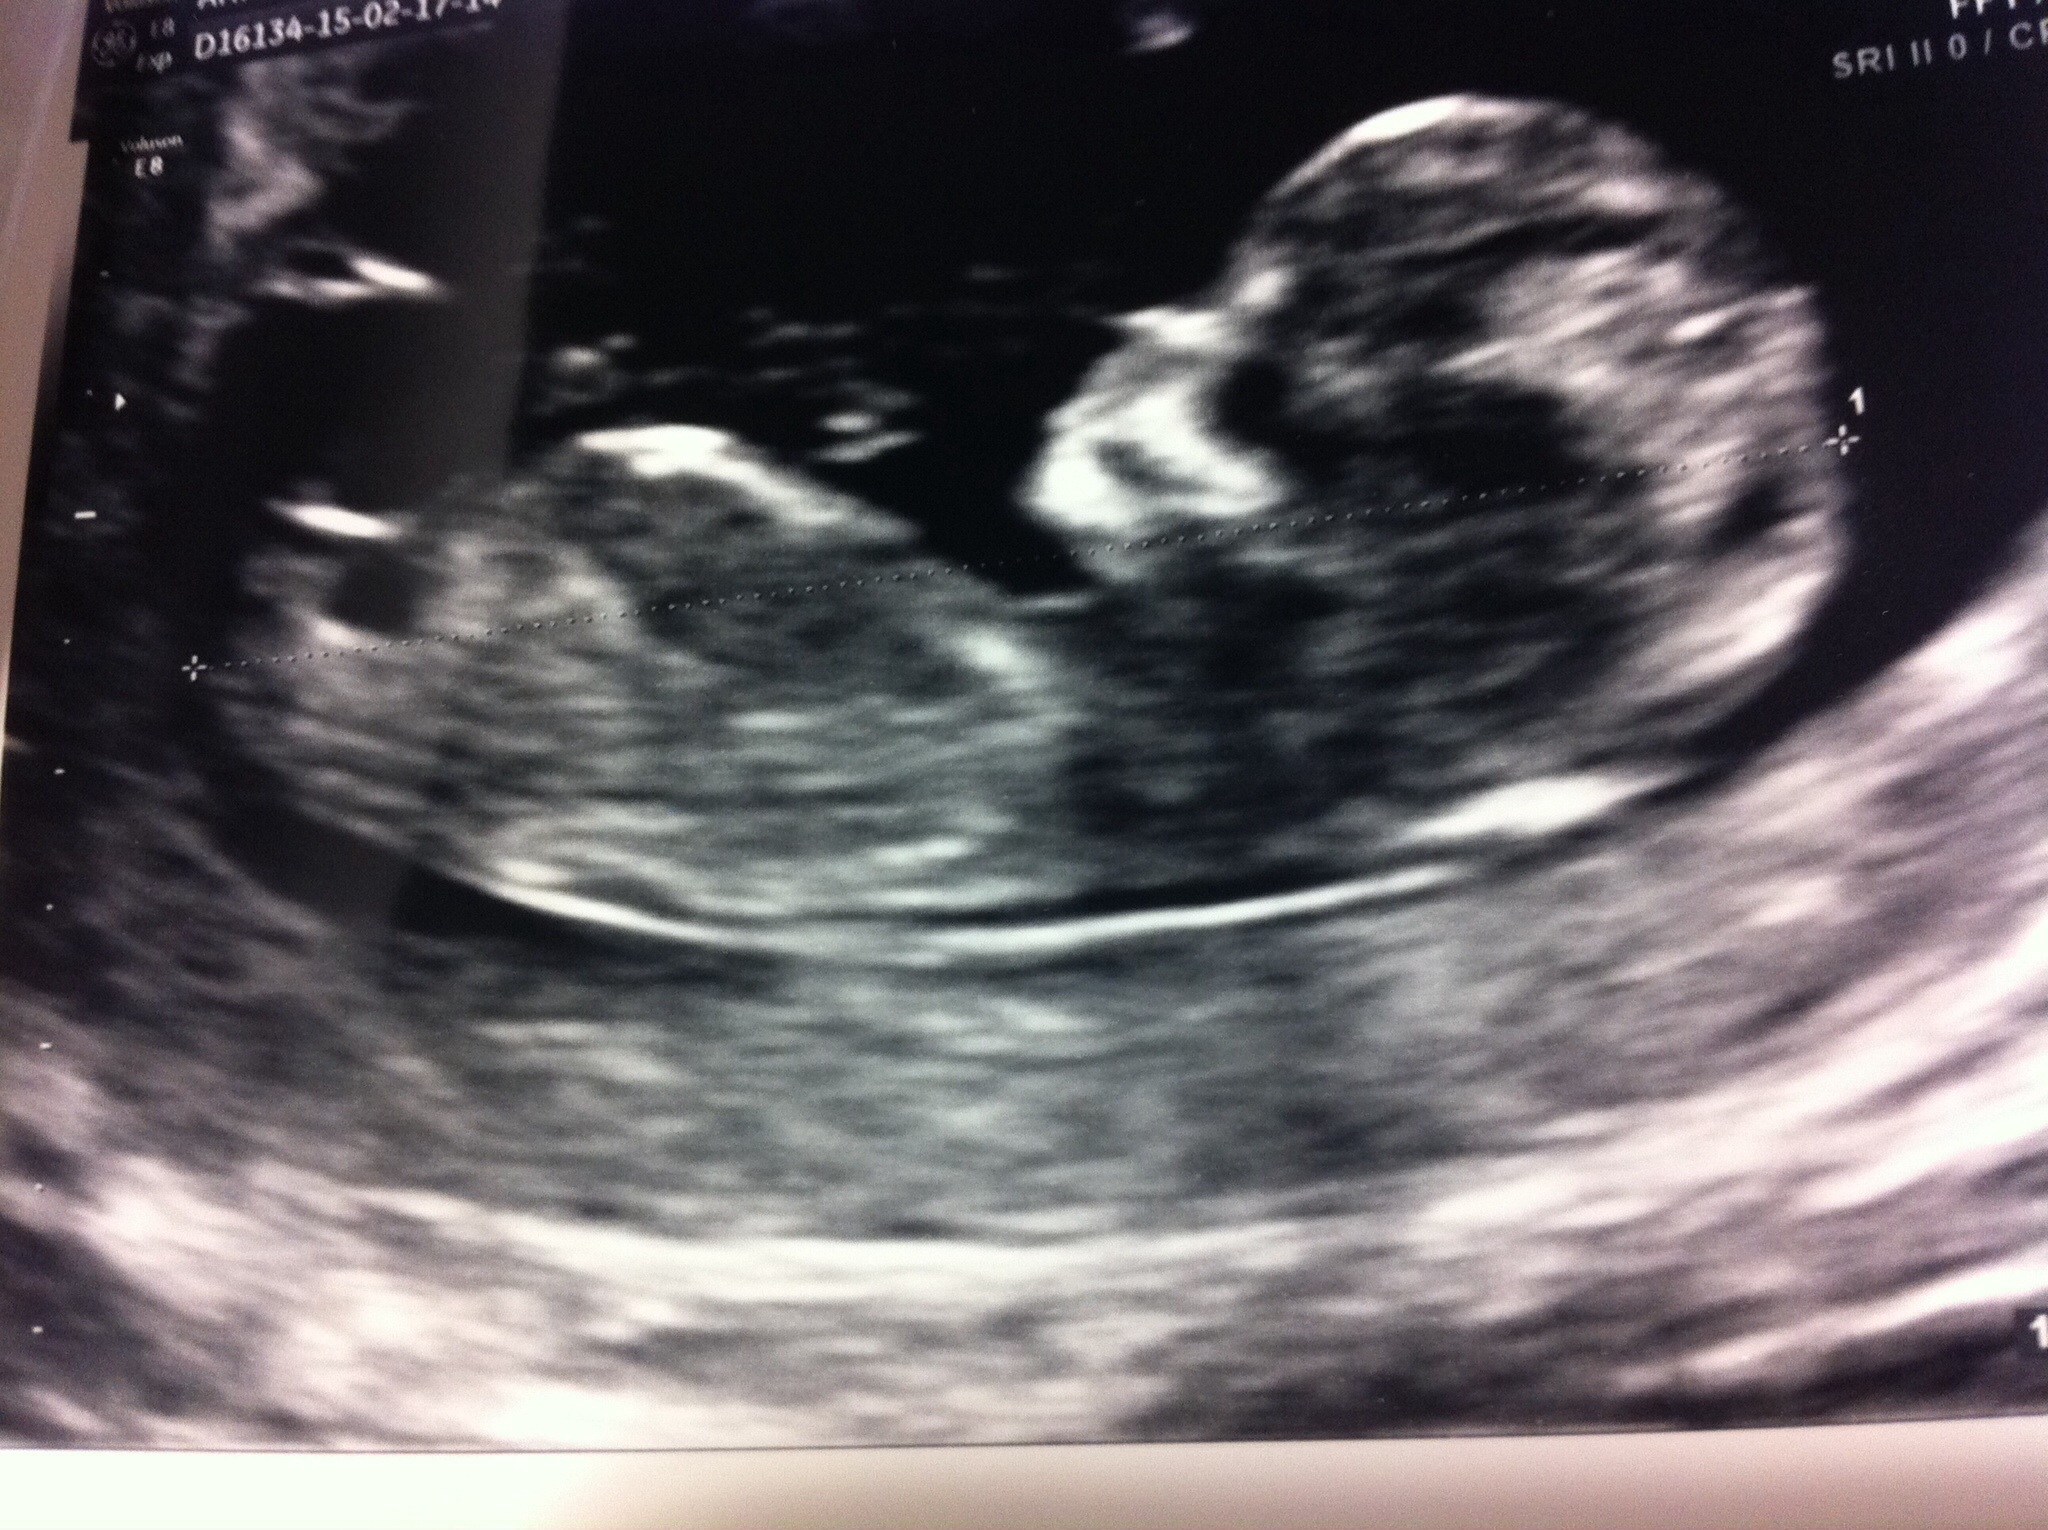

Attachment 23820This is my 12 weeks 2 days scan. Any guesses?2nd image is a shot of legs. Many thanks. Attachment 23819